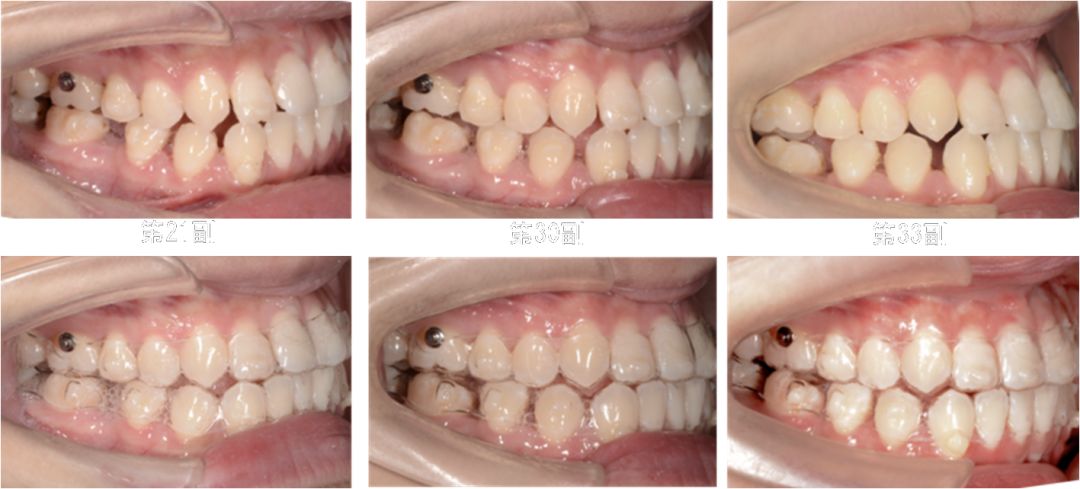

第8副,矫治器与牙面贴合,矫治过程中配合III类牵引,有利于尖牙、磨牙关系的改善。

第20副,矫治器与牙面贴合,近中矩形附件使矫治器对47牙有较好的固位,47牙与45相对移动,磨牙尖牙关系改善。

第30副矫治器时,其余牙位矫治器还是比较贴合,但是47牙近中出现了低合与矫治器间隙变大,嘱患者使用咬胶,利用矫治器的力量竖直47牙。

第33副,由于47牙持续的前倾,我们进行了矫治设计的反馈,患者由于干扰的去除,咬合支点的前移,出现了颌位的后退。因为这个原因,实现了比矫治设计更好的尖牙磨牙关系。所以这次我们反馈时提交的是cr位的咬合记录。